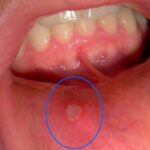

1. Luka Bulat di Dalam Mulut

Berwarna putih kekuningan dengan tepi kemerahan.